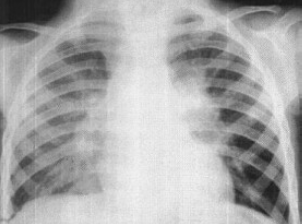

B.管电压

新生儿出生后出现气急、口吐白沫,呼吸微弱。床边X光片检查如图,最可能的诊断为()

A.新生儿肺炎

B.新生儿肺出血

C.新生儿白肺

D.新生儿心肌炎

E.先心病

点击查看答案